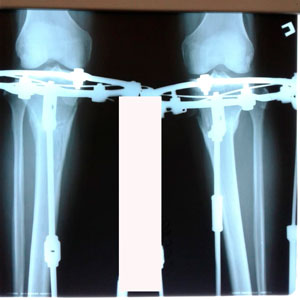

Исходник - 44 года.

Дата операции - 17.03.2020

Дата снятия аппаратов - 17.06.2020

Срок сращения - 90 дней.